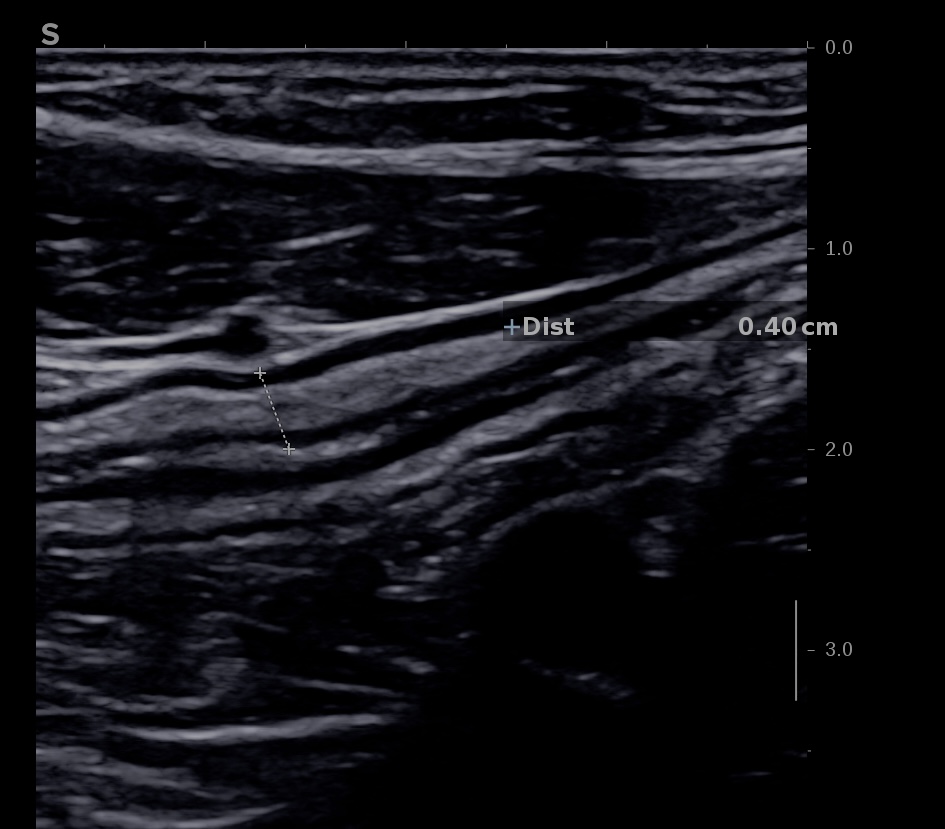

L'épaississement se mesure entre la muqueuse (hypoéchogène) et la musculeuse (hypoéchogène),

Ci dessous même portion avec et sans compression douce.

Il faut faire la moyenne de plusieurs mesures (≥3) en coupe longitudinale et transversale